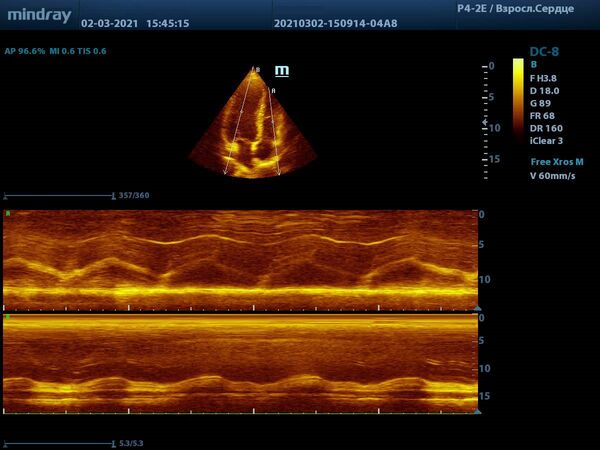

Продвинутые операторы диагностической техники также владеют методами оценки функции желудочков в режиме Free Xros – свободном М-режиме. Такие параметры как TAPSE позволяют быстро и удобно оценить сократительную функцию правого желудочка, нормальное значение движения амплитуды кольца трикуспидального клапана 17 миллиметров или более.

Левый желудочек не остается в стороне, для него есть показатель MAPSE – измеряется в М-режиме и пересчитывается во фракцию выброса левого желудочка. Показатель более 10 мм считают нормой. Для расчета фракции необходимо подставить значение в формулу EF = 4.8 × MAPSE (mm) + 5.8. Такой способ оценки применяется только у взрослых. Использование нескольких срезов одновременно с функцией Free Xross позволит оценить сразу оба желудочка, что сильно экономит время и силы к концу трудового дня.